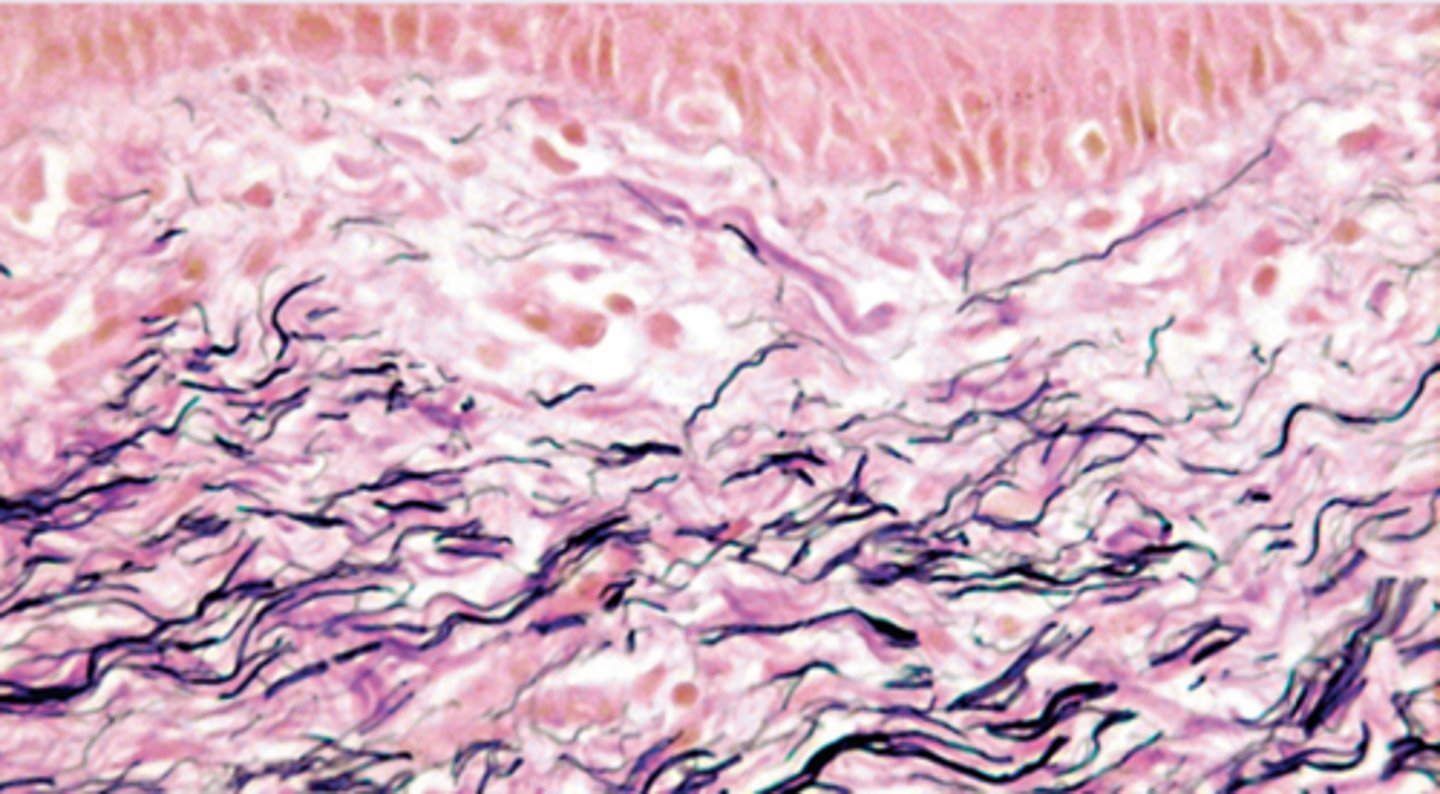

What is the Verhoeff-Van Gieson (VVG) stain used for?

To visualise Elastic Fibres.

What is the appearance of elastin and collagen when stained with VVG?

Elastin stains black/blue-black, while collagen stains red.